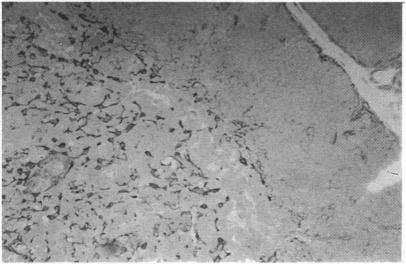

This paper presents a review of our current understanding of the nature of the thymic microenvironment, after briefly considering the major role of the gland. The epithelial cells and their products are of fundamental importance, and other cells of the macrophage series are implicated in most functional events. The embryological origin of the epithelium is still not clear, although disease conditions would suggest a single origin. Immigration and emigration of thymocytes is considered, and also the passage of antigens into the gland. The events within the thymus are under the control of the CNS acting through the innervation or via hormonal pathways. Both of these areas are considered in detail, especially thymic hormone origins, functions and interactions.

本文在简要阐述胸腺的主要作用之后,对我们目前对胸腺微环境本质的理解进行了综述。上皮细胞及其产物至关重要,巨噬细胞系列的其他细胞也参与了大多数功能活动。尽管疾病情况表明上皮细胞有单一来源,但其胚胎起源仍不清楚。本文考虑了胸腺细胞的迁入和迁出,以及抗原进入胸腺的过程。胸腺内的活动受中枢神经系统通过神经支配或激素途径的控制。对这两个方面都进行了详细讨论,尤其是胸腺激素的起源、功能及相互作用。